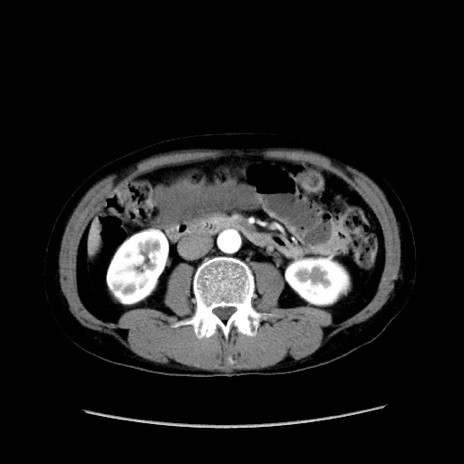

症例37(横断像)

【症例】40歳代 男性

【主訴】腹痛

【現病歴】4時間ほど前に電車に乗車中に臍部上より腹痛出現。徐々に増悪し起立困難となり、救急外来受診。生ものは数日食べていない。今朝お雑煮を食べた。

【身体所見】BT 36.8℃、BP 117/84mmHg、HR 91/min、SpO2 97%、苦悶様、腹部:臍上部広範囲圧痛あり、反跳痛±

【データ】WBC 8100、CRP 0.03